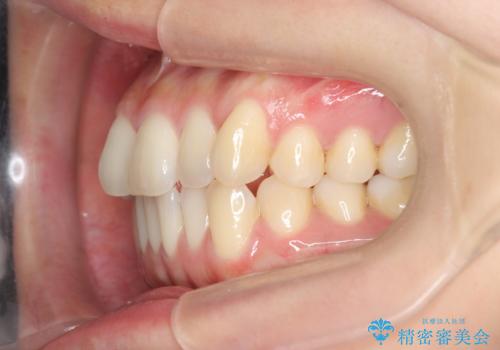

前歯のねじれを改善 マウスピース矯正インビザライン

左側の奥歯は後方移動を行うことで、理想的な噛み合わせに整えるとともに、前歯の突出感も同時に改善することができました。